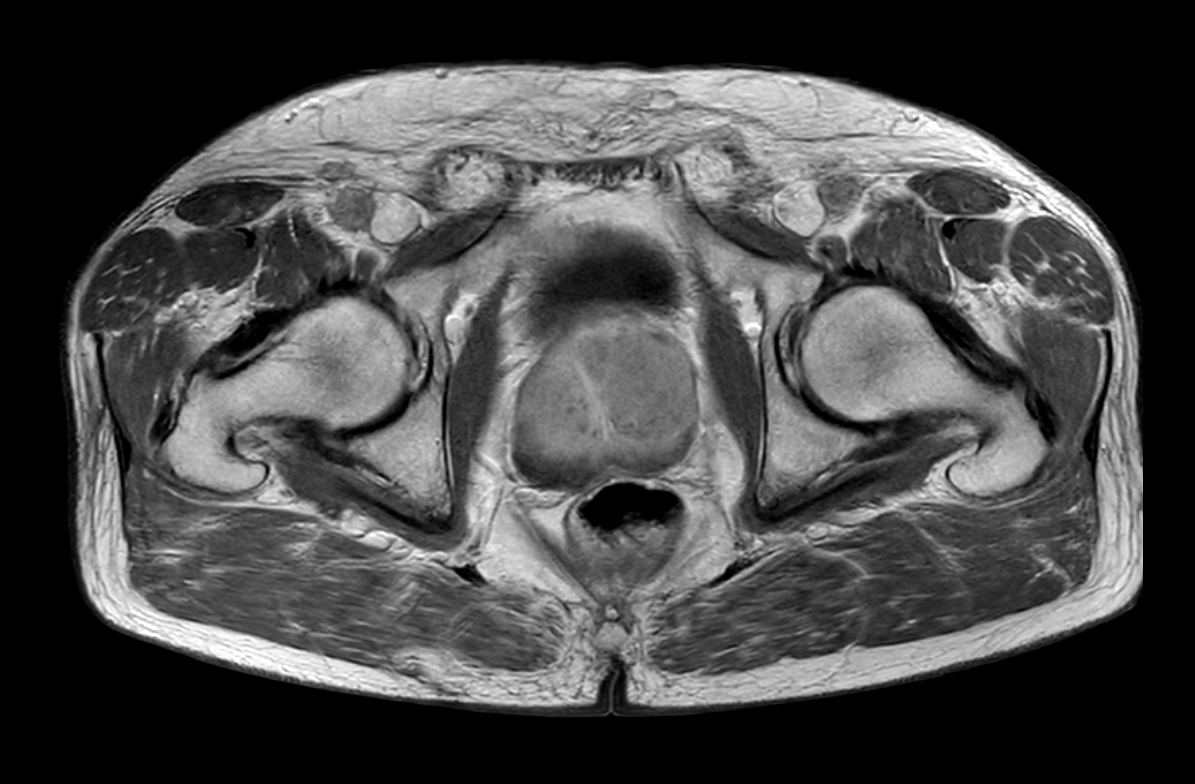

Axial T2w TSE FatSat